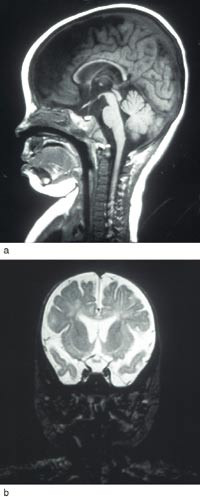

Vel ti månader gamal vart ho overflytta til Rikshospitalet. Ho var komatøs ved innlegginga. EEG var markert patologisk. Cerebral MR viste auka væske over båe frontal- og temporallappane. Det supratentorielle ventrikkelsystemet var litt markert. Corpus callosum var utvikla i heile lengda, men var tynnare enn forventa for alderen. Myeliniseringsgraden var normal (fig 1). Under eit langvarig krampeanfall fekk ho pyridoksin 100 mg intravenøst, og krampane stoppa etter 20 – 30 minutt. Ho vart sett på pyridoksin 100 mg dagleg i tillegg til valproat, klonazepam og vigabatrin.

Etter start av pyridoksintilførsel byrja ei rask motorisk og mental utvikling. Ho kunne gå ved 18 månaders alder. Ved 16 månaders alder hadde ho enkeltord, 37 månader gamal 5 – 6 ords setningar. Frå 3 1/2 års alder vart det observert problem med balanse og grovmotorikk. Ho vart reinsleg og tørr i fireårsalderen. Hovudomkrinsen låg i seks månaders alder 1 cm under 2,5-percentilen, under pyridoksinbehandling auka han gradvis til 25-percentilen. Cerebral MR var normal ved vel åtte års alder (fig 2). Fem år og åtte månader gamal viste ein ikkje-verbal evnetest samsvar mellom kronologisk alder og mental utvikling. Ho går no i vanleg skule og fylgjer klassetrinnet sitt. Men ho har slite med språklege og matematiske omgrep – lese-, tal- og mengdeforståing.

Det finst ingen diagnostiske laboratorietestar. EEG kan vise teikn på diffus og fokal cerebral dysfunksjon, men ingen spesifikke mønster (4). Cerebral CT og MR har vist uventa høg prevalens av strukturelle defektar i sentralnervesystemet, men ingen typiske abnormitetar. Det er funne varierande grad av atrofi av grå og kvit susbstans og tynn corpus callosum, som hjå vår pasient, likeins cerebellar hypoplasi og mega cisterna magna (8, 10). Inadekvat pyridoksinbehandling synest å kunne medføre progredierande atrofi av grå og kvit substans (10).

Ubehandla døyr pasienten i ein alvorleg krampetilstand. Alderen ved dødstidspunktet hjå 31 ubehandla pasientar varierte mellom to dagar og 16 månader, gjennomsnittleg 3 1/2 månad (13). Prognosen ser ut til å vere betre hjå dei som debuterer etter ein månads alder (3). Det synest å vere ein viss samanheng mellom prognosen og tidsromet frå krampedebut til behandlingsstart. Ved tidleg krampedebut er meir enn ei vekes behandlingsutsetjing assosiert med aukande fare for utvikling av lærevanskar og cerebral parese. Vår pasient illustrerer at prognosen kan vere god når pyridoksindoseringa er adekvat, sjølv om behandling vart starta relativt seint. I eit nordengelsk materiale med seks pasientar lærde borna å gå då dei var mellom 12 og 40 månader gamle, og dei byrja å tale då dei var mellom 12 og 36 månader. Ingen utvikla cerebral parese, men dei fleste hadde ekspressive språkvanskar, men relativt intakt språkforståing. IQ varierte frå under 50 til 90 (8). Dersom pyridoksintilførselen er for låg eller uregelmessig, kan det oppstå hjerneatrofi og forseinka utvikling av alvorleg grad (10). Utviklinga hjå vår pasient kan tyde på at høg pyridoksindose kan føre til ei positiv utvikling, bedømt både klinisk og etter cerebral MR (fig 1, fig 2).